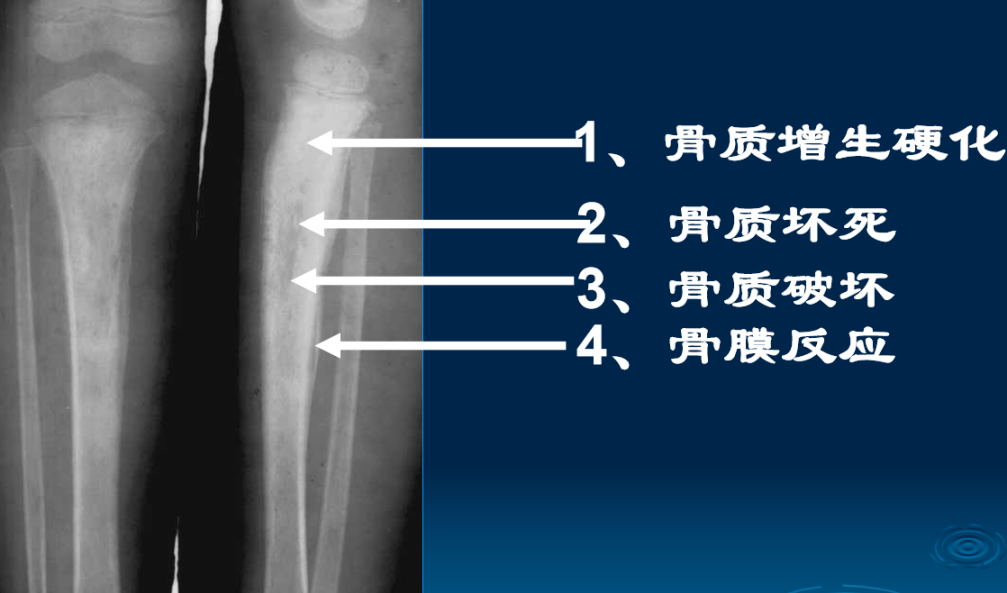

影像学表现:(1)X线平片:早期(3-5天)皮下软组织肿胀,肌间隙模糊;两周后(10-14天始)骨质破坏、骨膜增生(层状),骨膜新生骨包壳形成;部分形成死骨(抗生素广泛应用致少见)。

2周以后:1、骨质疏松:局限;2、骨质破坏为主→骨干;3、骨膜增生:骨包壳;4、骨质坏死:死骨 ;5、轻度骨质增生